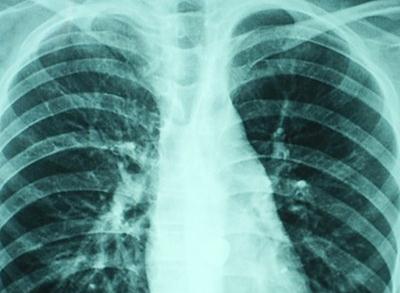

5.X線胸片:大片狀陰影,多見肺底和中部,個別為粟粒狀陰影,但在短期內(nèi)可有變化。

8.臨床癥狀輕而肺部X線征象嚴(yán)重;使用抗生素,病勢惡化;用抗真菌藥物治療顯效。